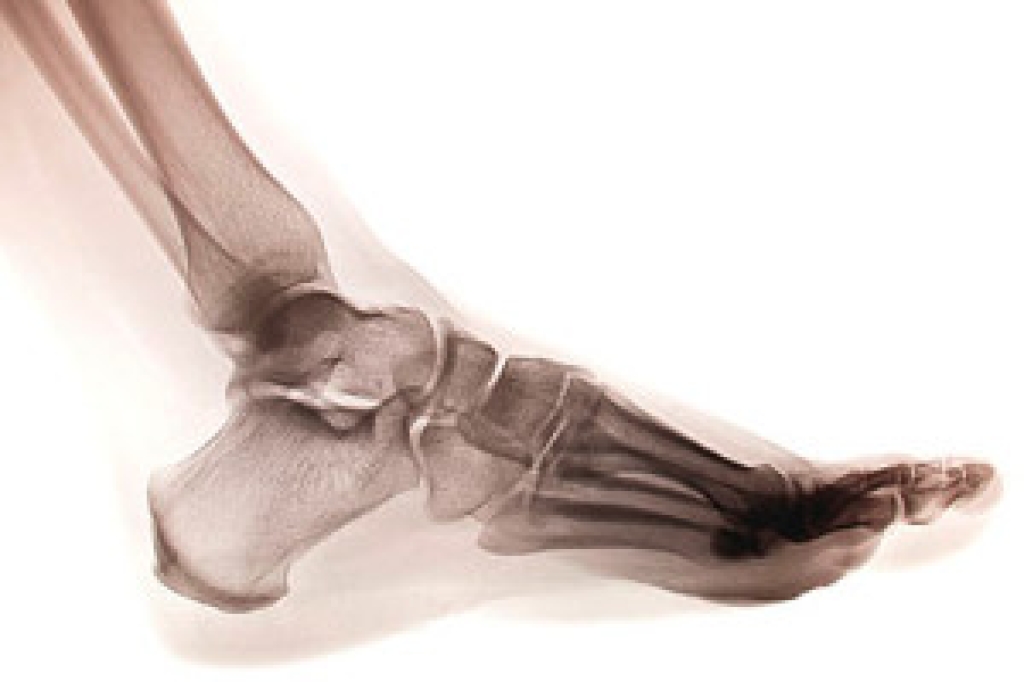

There are five metatarsal bones found in the foot, each connecting the heel/arch to the toes. These long bones play a critical role in helping the foot function. However, the metatarsal bones can suffer from what is known as a stress fracture, a crack in the bone that develops from repeated trauma. The metatarsal bones are the second most common bones in the lower limbs to suffer from stress fractures, the first being the tibia leg bone. Of the five metatarsals, the second and third metatarsal bones are the most commonly afflicted. One common symptom of a metatarsal stress fracture is pain felt in the foot when walking or running. If you are running long distances and are not wearing the right kind of footwear, you might be increasing your risk of developing a stress fracture. Contact a podiatrist today for more information about metatarsal stress fractures.

Stress fractures occur in the foot and ankle when muscles in these areas weaken from too much or too little use. The feet and ankles then lose support when walking or running from the impact of the ground. Since there is no protection, the bones receive the full impact of each step. Stress on the feet can cause cracks to form in the bones, thus creating stress fractures.